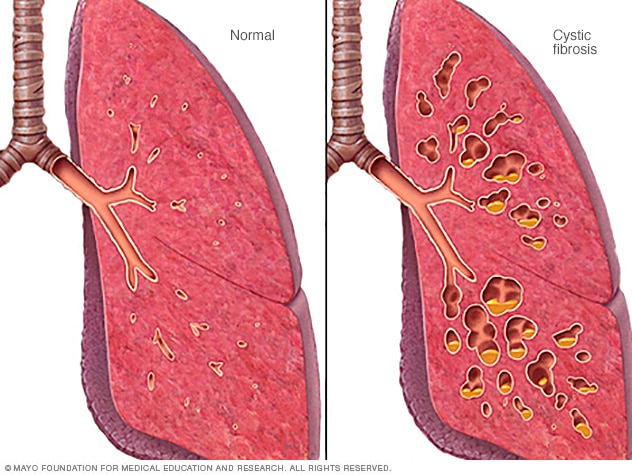

Cystic fibrosis

In cystic fibrosis, the airways fill with thick, sticky mucus, making it difficult to breathe. The thick mucus is also an ideal breeding ground for bacteria and fungi.

CF affects the cells that make mucus, sweat and digestive juices. These fluids, also called secretions, are usually thin and slippery to protect the body's internal tubes and ducts and make them smooth pathways. But in people with CF, a changed gene causes the secretions to become sticky and thick. The secretions plug up pathways, especially in the lungs and pancreas.

In cystic fibrosis, the lungs are most commonly affected. The thick and sticky mucus that happens with CF clogs the tubes that carry air in and out of the lungs. This can cause symptoms such as:

- Damaged airways. Cystic fibrosis is one of the leading causes of damaged airways, a long-term lung condition called bronchiectasis. Bronchiectasis results in widening and scarring of the airways. This makes it harder to move air in and out of the lungs and clear mucus from the airways.

- Ongoing infections. Thick mucus in the lungs and sinuses makes a place for bacteria and fungi to live and grow. Sinus infections, bronchitis or pneumonia are common and may happen repeatedly. Infections with bacteria that don't respond to antibiotics and are difficult to treat is common too.